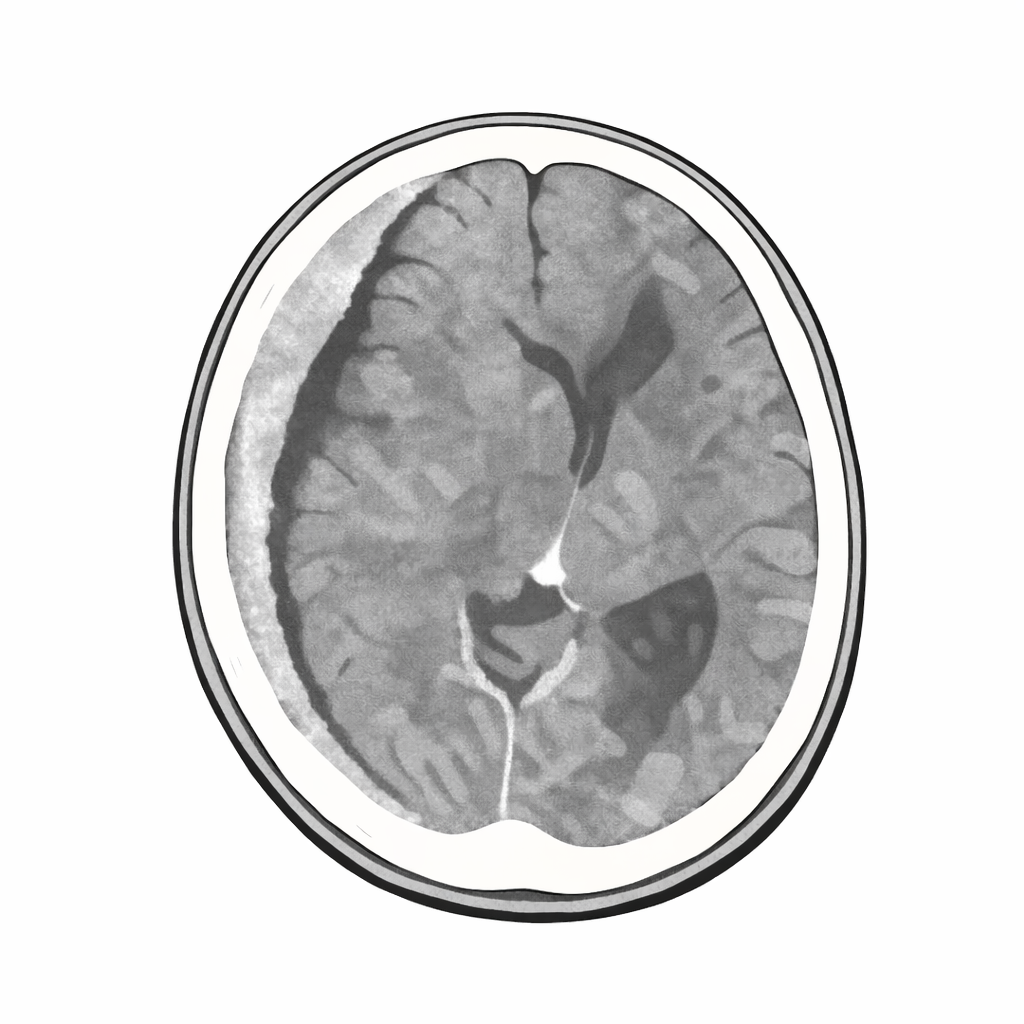

・くも膜下出血ではシルビウス裂に高吸収域がみられる

CTでは 凸レンズ状(両凸型) に見える。

CTでは 三日月型(半月状) に見える。

硬膜外血腫

→ 硬膜が頭蓋骨にへばりついている

→ 剥がされて内側に膨らむ

→ 両凸型

硬膜下血腫

→ 硬膜とくも膜の間は広がれる

→ さーっと広がる

→ 三日月型